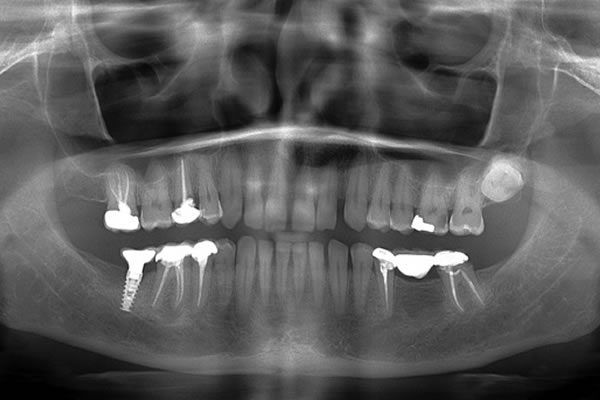

VELMENI for Dentists® 2D

VELMENI is as easy to use as it is powerful. Scan 2D radiographs to increase detection accuracy by 30%. FDA cleared for 2D Panoramic, Bitewing and Periapical X-Rays.